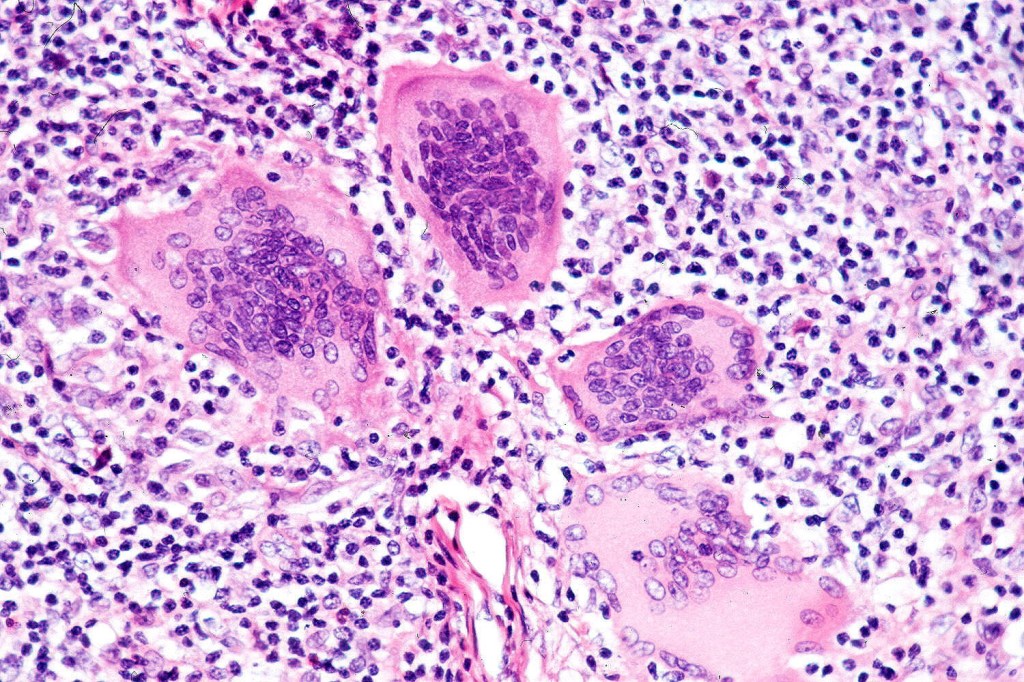

•Atypical, hyperchromatic lymphocytes, Sezary cells, histiocytes, plasma cells, eosinophils & characteristic multinucleate giant cells (innumerable nuclei resembling a shoal of fish)

•Lymphophagocytosis is generally marked

•Discrete granulomata often evident & in some cases may be the dominant feature obscuring the background lymphomatous infiltrate